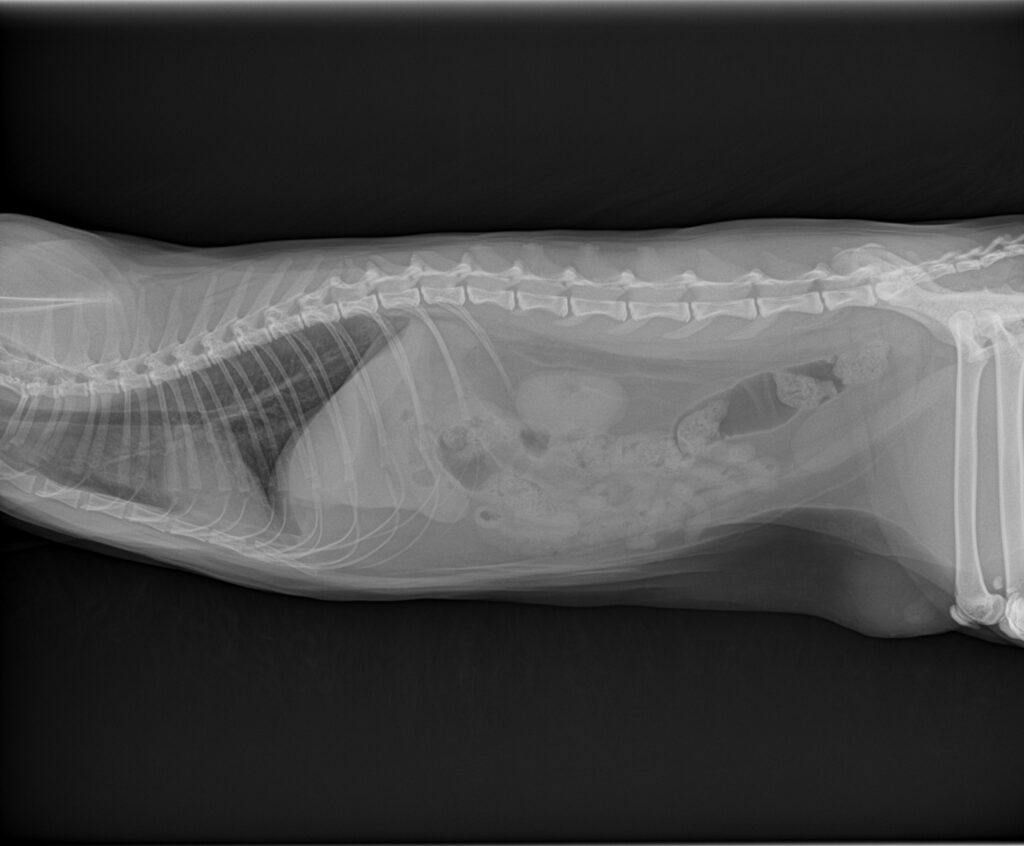

来院時のレントゲン検査ではひも状異物に特有なつづれ陰影などは認められませんでしたが、超音波検査で胃の出口にシャドーを引く丸い異物陰影と十二指腸へ続く線状の異物陰影を認めました。